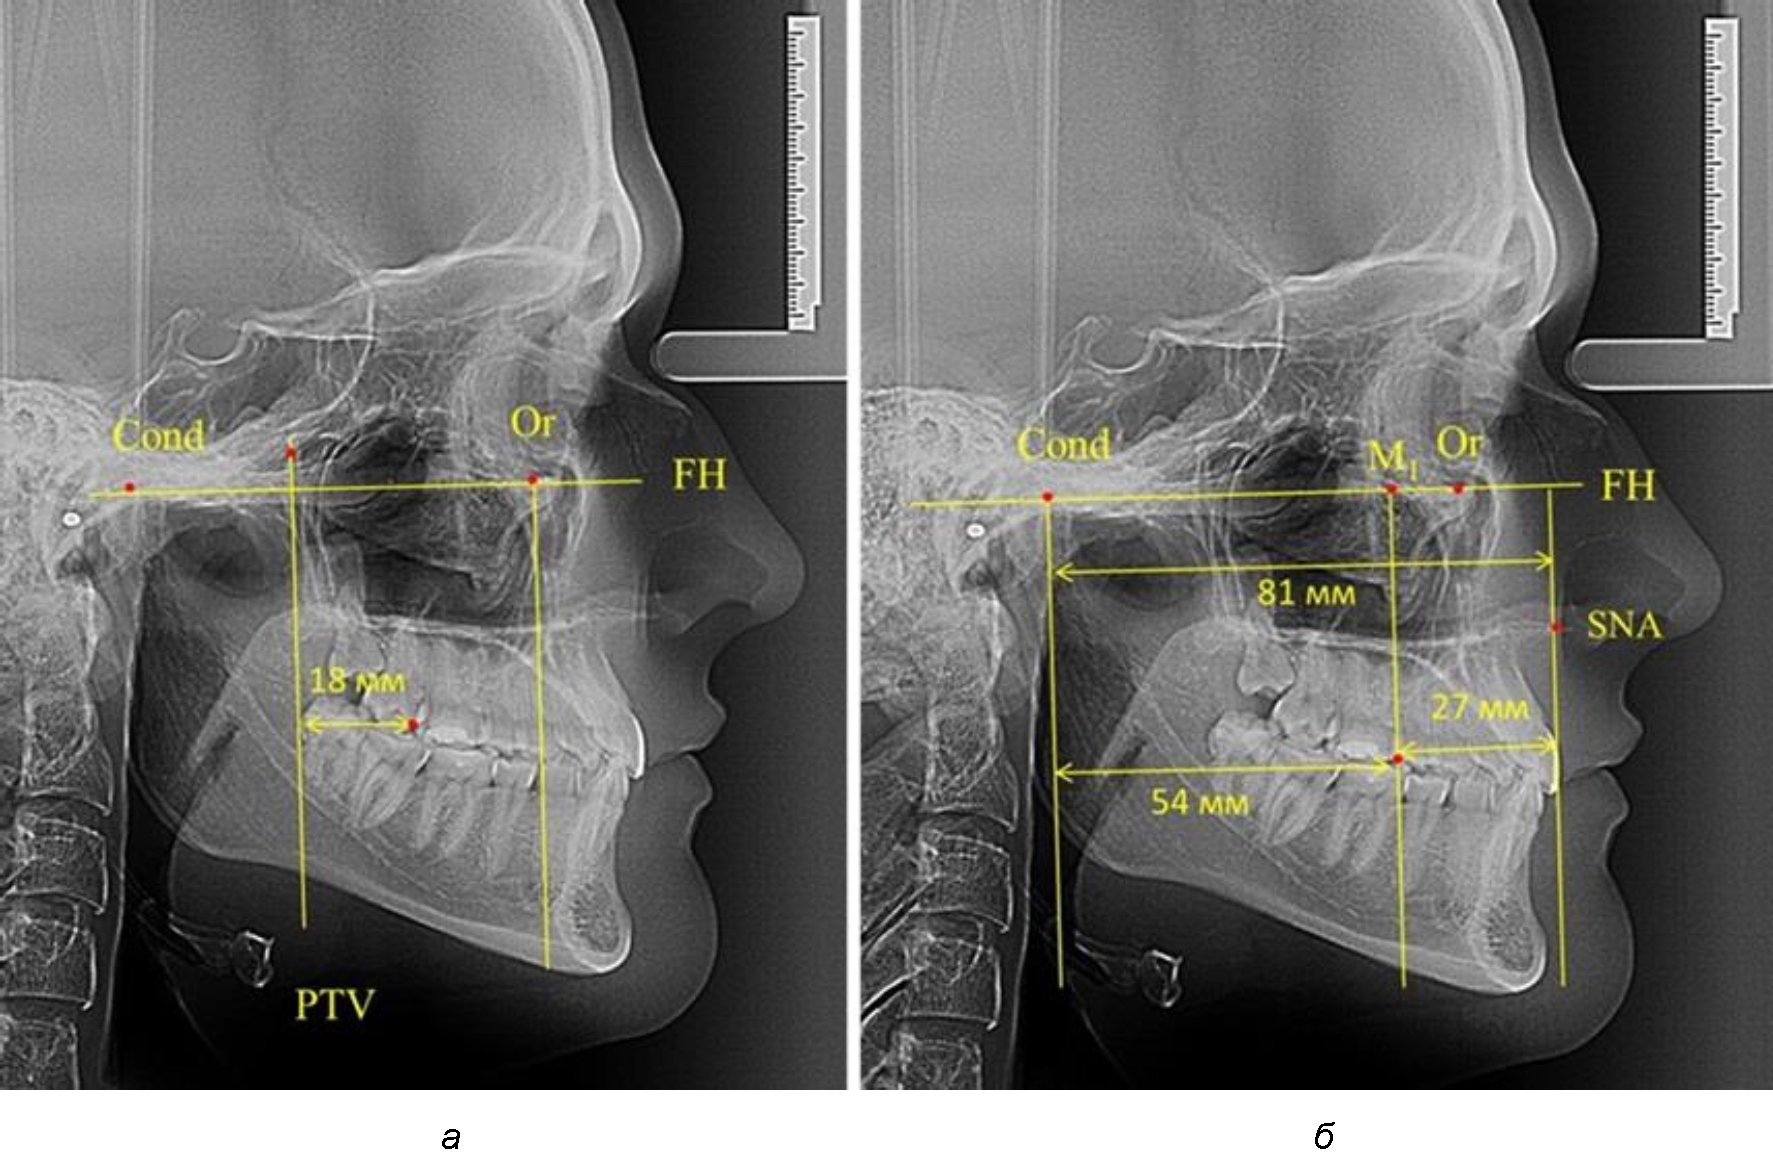

Согласно указанному методу на рентгенограммах проводили Франкфуртскую горизонталь. Учитывая мнения специалистов относительно ориентиров для построения и вариабельность положения наружного слухового прохода, в качестве задней точки использовали верхнюю выпуклость суставной головки нижней челюсти («Cond»). Передняя точка традиционно располагалась на нижнем крае глазницы и определялась как орбитальная точка Or.

Находили положение точки Pt, которая располагалась на пересечении нижнего края круглого отверстия и задней стенки крыловидно-верхнечелюстной щели, и перпендикулярно к Франкфуртской горизонтали проводили крыловидную вертикальную линию, которую принято обозначать как плоскость PTV. Расстояние от крыловидной вертикальной плоскости PTV до дистальной поверхности верхнего первого постоянного моляра определяло его положение, которое, по мнению R. E. McDonald, соответствовало возрасту пациента, увеличенному на 3 мм.

При проведении анализа к Франкфуртской горизонтали проводили передний и задний перпендикуляры. Передний спинальный перпендикуляр проходил через выступающую точку передней носовой ости (spina nasalis anterior – SNA), а задний суставной перпендикуляр опускали из кондилярной точки Cond. Молярный перпендикуляр проводили через медиальную поверхность первого постоянного моляра. Указанная вертикаль отделяла замещающие зубы постоянного прикуса от добавочных зубов (постоянных моляров), что вполне логично для анализа положения первых постоянных моляров в гнатическом комплексе (рис. 1).

Рис. 1. Метод определения положения первых верхних моляров по Ralph E. McDonald (а) и по предложенному методу (б)